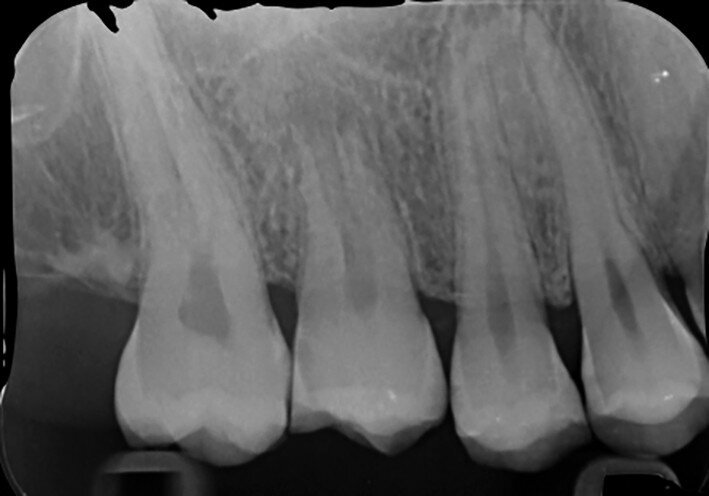

Fig. 3: Pre-op periapical radiograph.

A 47-year-old male patient in a good medical condition and a non-smoker was referred to our dental practice for endodontic retreatment of the right maxillary second molar. The dental history revealed that the tooth had been endodontically treated three months before because of acute pulpitis. After the treatment, the patient complained of pain on chewing. Antibiotics and a non-steroidal anti-inflammatory drug were prescribed, but the pain remained. After a month, a sinus tract appeared. The tooth was retreated in another practice without success. The clinical inspection revealed the presence of a sinus tract near the apical region of tooth #17. The tooth had been prepared for a full crown, but was without even a temporary crown, and the access cavity had been closed with temporary filling material. Cracks were evident on the buccal and mesial surfaces. Periodontal probing showed a deep pocket (> 12 mm) on the distal aspect of the root trunk (Figs. 1 & 2). The periapical radiograph showed a radiolucency between the roots of the second and third molars. The radiographic appearance of the endodontic treatment was good, without clear evidence of periapical radiolucencies (Fig. 3). A perforation of the pulp chamber floor was suspected. A CBCT scan was performed (Figs. 4–7), and it confirmed the suspicion of perforation, along with the presence of a large periradicular radiolucency and an unfavourable root shape.